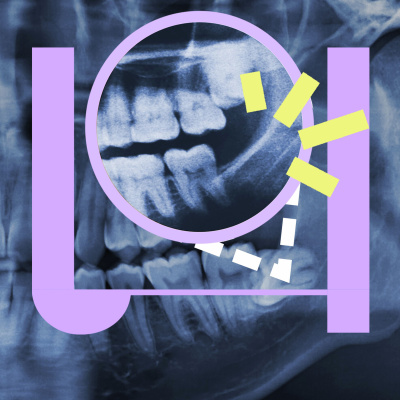

Ongeveer 20 procent van de mensen mist bij geboorte één of meerdere verstandskiezen. Niet zo erg, want eigenlijk hebben we die extra kiezen niet meer nodig. Vroeger sleten onze tanden veel sneller en was het handig dat er rond je twintigste nog een derde set kiezen doorkwam. Maar tegenwoordig hebben verstandskiezen nauwelijks meer een functie, omdat we ons eten koken en onze tanden beter verzorgen. Dat ze langzaam verdwijnen, heeft alles te maken met evolutie; als iets niet meer nuttig is, dan kan het in de loop van de tijd verdwijnen. Dat geldt niet alleen voor verstandskiezen, maar ook bijvoorbeeld voor een spiertje in onze onderarm of het vermogen om je oren te bewegen. Yanell Braumuller (Naturalis | Universiteit Leiden) onderzoekt dit soort evolutionaire overblijfsels bij mensen en dieren. Zulke ‘restanten’ kunnen namelijk nog meer evolutionaire mysteries ontrafelen. Hoe dat zit legt hij uit in deze aflevering!See omnystudio.com/listener for privacy information.